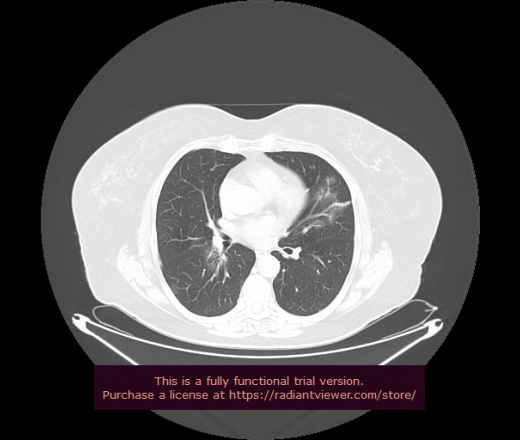

Уважаемые коллеги, если имеется интерес, сможете ли Вы спрогнозировать дальнейшее +-одинаковое течение процесса у 4 данных разных пациентов? Зацепиться где-то можно очень просто, где-то нельзя.